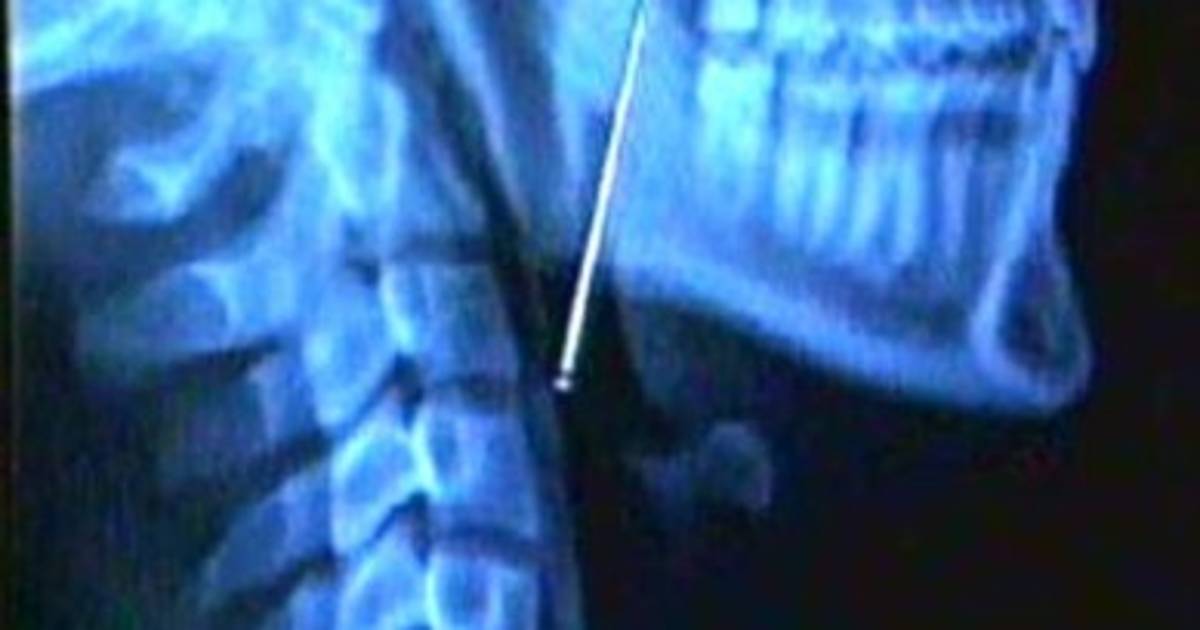

Cuando su madre Angelina Mayta la llevó al hospital, la radiografía que le hicieron reveló que el objeto se encontraba en su garganta.

Los médicos le indicaron que la menor corre peligro, pues si el alfiler golpease algún órgano, podría ocasionar una hemorragia e incluso la muerte.

Sin embargo, precisaron que esperarán a que el objeto salga por las vías naturales y solo operarán de ser necesario.